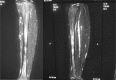

Posterior tibial stress fractures are more frequent than anterior tibial stress fractures, and they are considered to have a good prognosis for returning to sports; cases leading to a complete fracture are rare. A 17-year-old male involved in high school athletics middle-distance running had a 3-week history of pain with training. He was running up to 300 km/week on streets and cross-country in an even distribution. He had posterior tibial stress fractures, but despite the lower leg pain, he continued running. One year later, he was brought to the emergency department after having sustained an injury to the right lower leg while running in a middle-distance race; bilateral tibial stress fractures, with one side complete and the opposite side incomplete, had developed simultaneously. This relatively rare case of bilateral posterior stress fractures, with one side a complete fracture and the opposite side an incomplete fracture, that was treated surgically via exchange intramedullary nailing is reported. The patient could begin light jogging from 3 months after surgery and was without symptoms at 5 months after surgery. He could resume middle-distance racing after 1 year. Posterior tibial cortical fractures are more common and respond better to conservative treatment than anterior tibial stress fractures, and they are a common fracture type in runners. We believe that close, careful follow-up is necessary if patients continue excessive training.